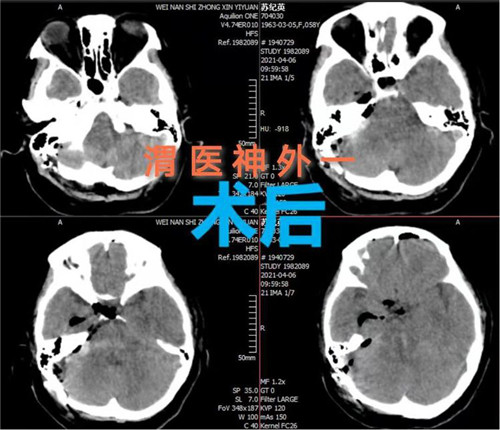

4月5日,市中心医院神经外科一病区通过开颅手术成功救治一例脑干出血患者。该手术的实施和成功填补渭南市该项领域空白,达到省级先进水平。

患者女性,58岁,突然意识不清3小时,行头颅CT检查提示:脑干出血。入院时患者深度昏迷,GCS评分6分。患者脑出血部位特殊,病情危重,手术风险大,并且既往有高血压、糖尿病史,围手术期随时有死亡可能。神经外科一病区赵金安主任带领团队评估手术风险,立刻上报医院,并和家属及时沟通,经反复讨论后最后决定实施开颅脑干血肿清除术:一级入路为右侧乙状窦后入路;二级入路为三叉神经下一面听神经上脑桥侧安全区。

手术计划制定后,即刻安排手术,手术麻醉科确定了由麻醉医师钟永慧、配合护师党海婷和马丹组成的麻醉护理团队。手术历时近4个小时,手术过程患者生命体征平稳,术中总出血量约50毫升,术后患者恢复自主呼吸。术后次日患者生命体征平稳,意识恢复,右侧肢体活动正常,左侧肢体活动正在恢复中。